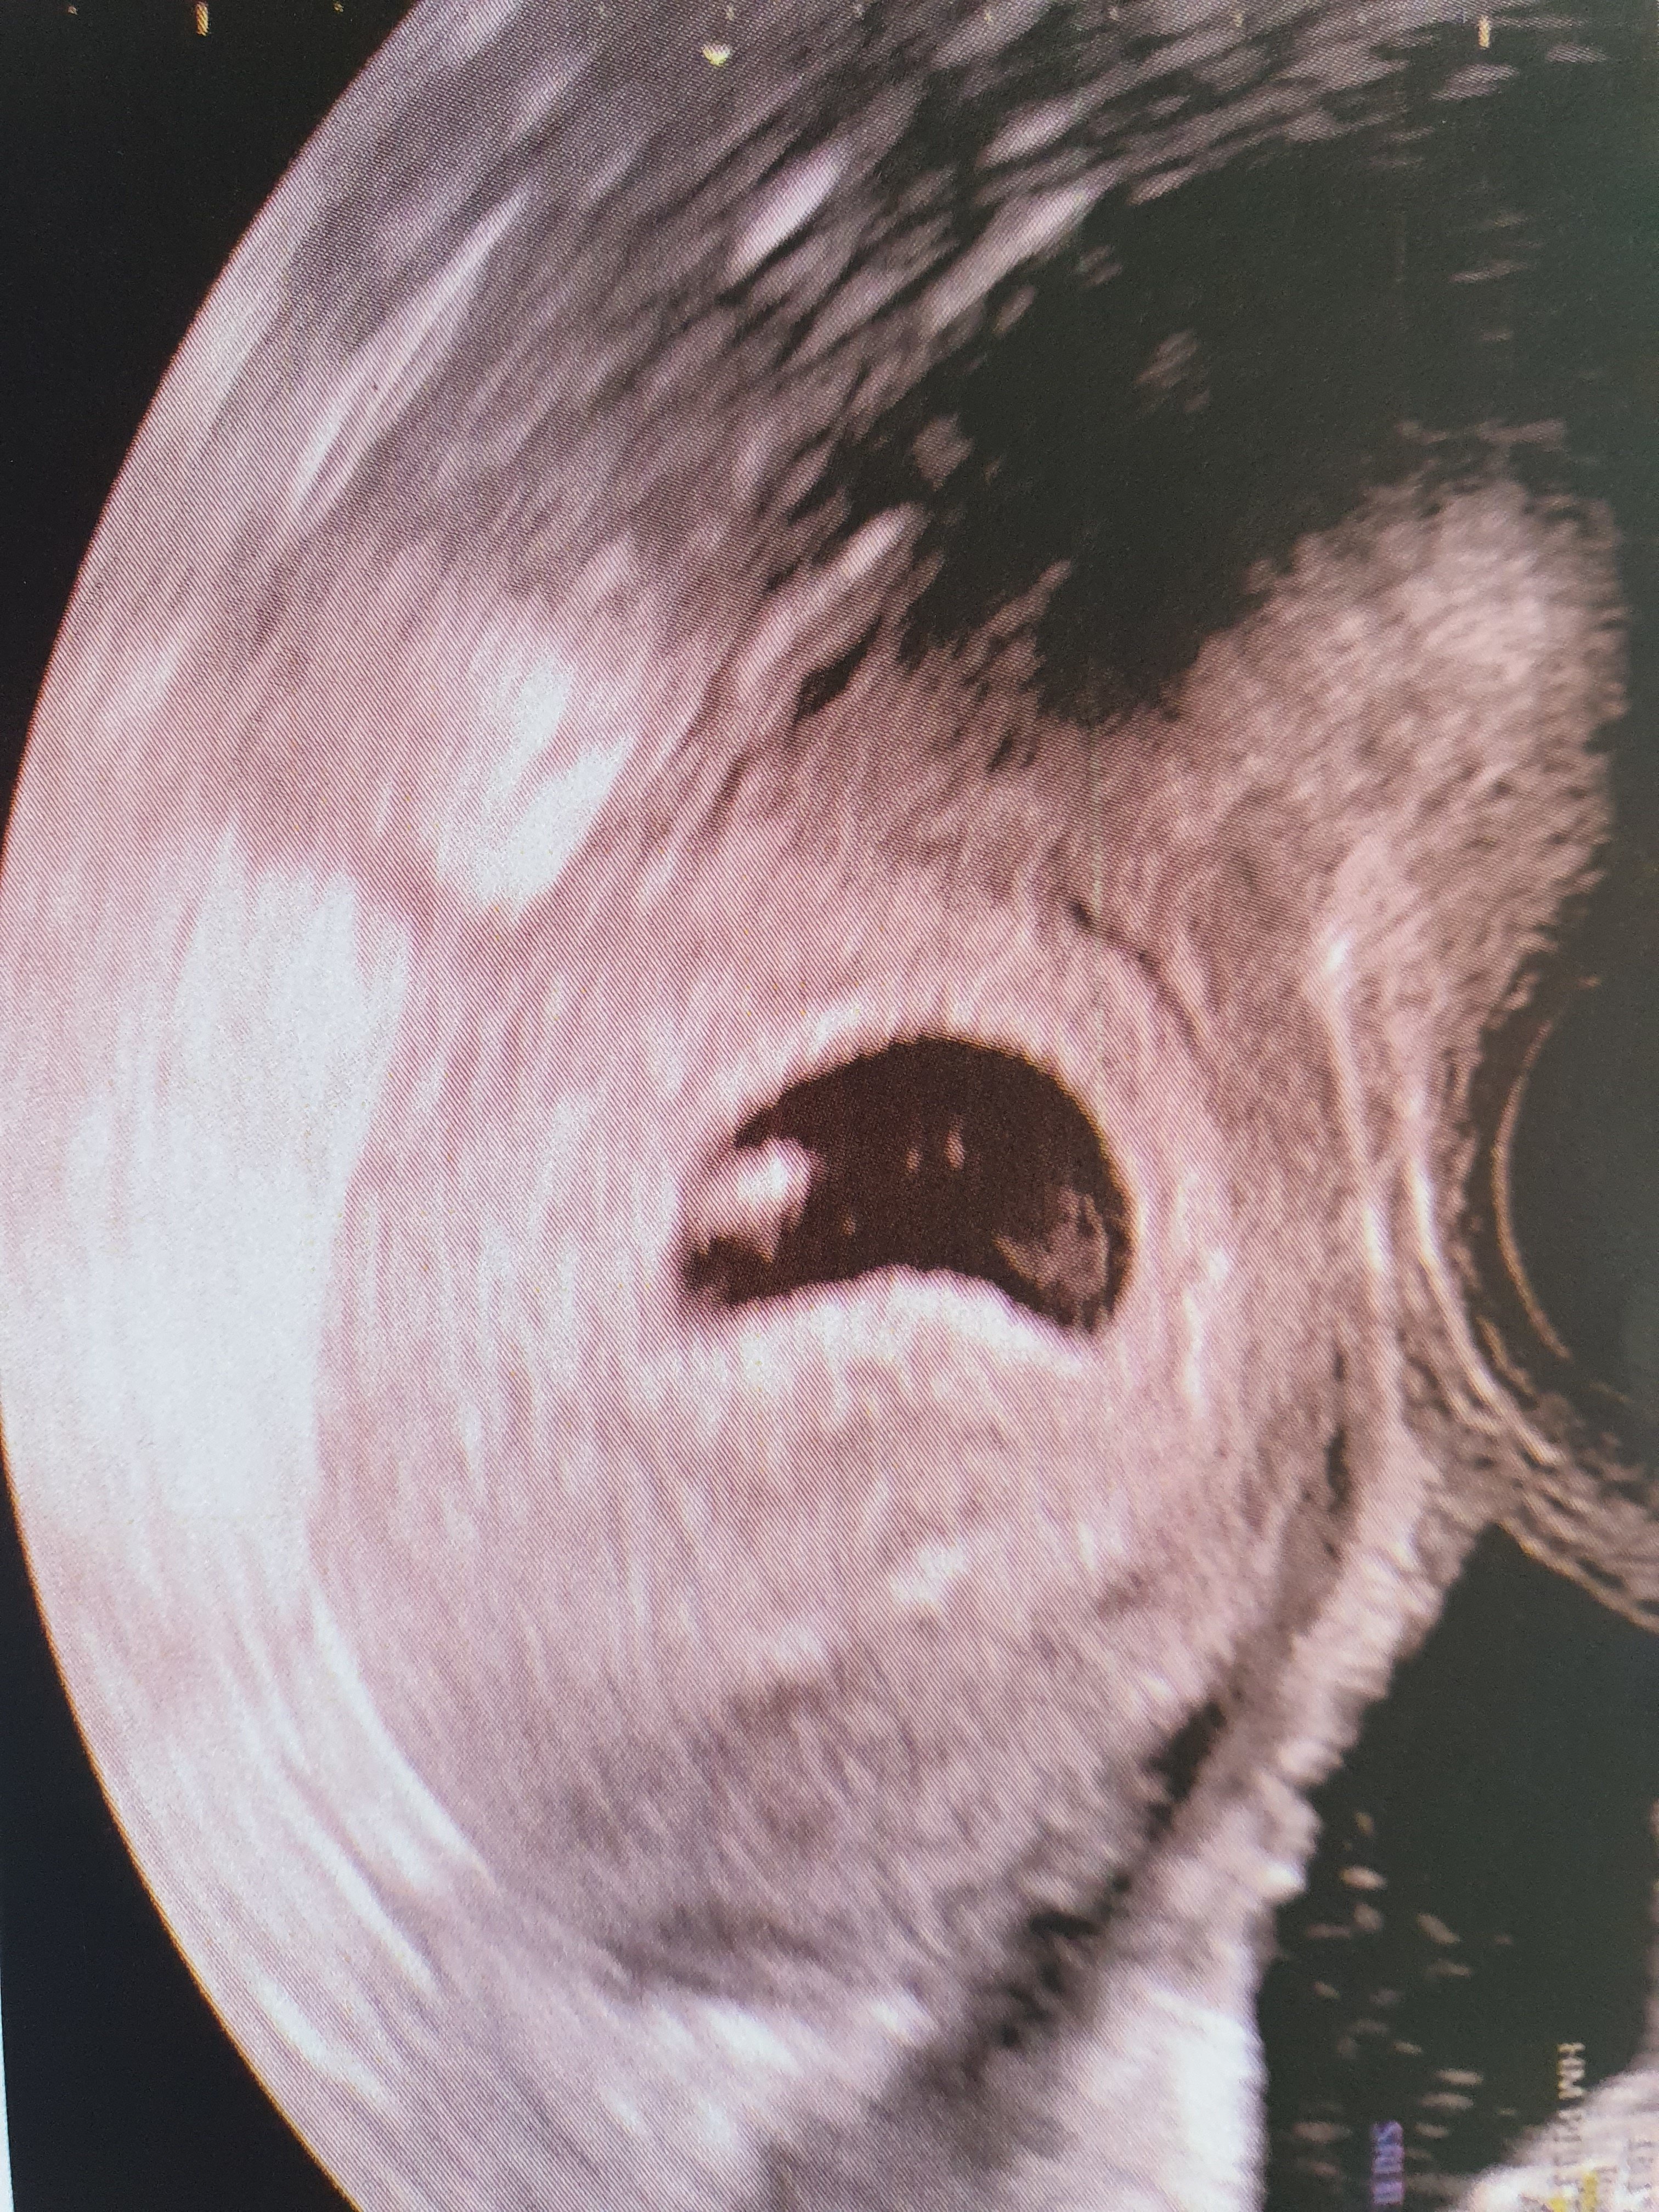

Cześć dziewczyny, wczoraj byłam na pierwszej wizycie z USG wynika że to 6t2d póki co wszystko jest w najlepszym porządku, serducho maleństwa wali ❤ To najpiękniejsze uczucie jakie kiedykolwiek miałam. Termin 5 stycznia 2020. Trafiłam naprawdę do dobrego lekarza, który mnie uspokoił.